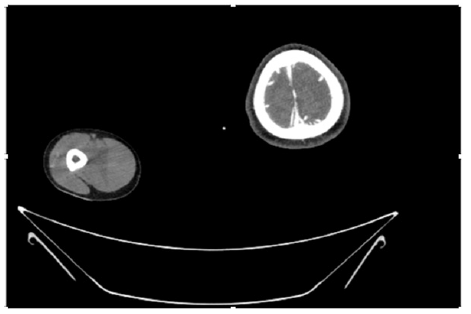

55-years-old chronic smoker had acute, severe pain in the right upper limb for one week; it was cold upto mid arm with skin discoloration. He also noticed numbness and weakness of movement of elbow joint. He underwent below elbow amputation in February 2023 for acute ischemia of left upper limb. He was a current chronic smoker; 15 pack year. General condition was weak; temperature was normal; blood pressure was 100/60mmHg; heart rate was 92/minutes with sinus rhythm; SpO2 was 97% on air; heart was normal. In lower extremities, all peripheral pulses were intact. Local Examination of right upper limb revealed as follows: tenderness; coldness; discoloration; decreased motor function and sensory modalities. Axillary, brachial and radial pulses were not palpable. Hand-held Doppler failed to detect any signal in arterial system; therefore, we arranged for emergency embolectomy. complete occlusion of right upper limb arterial system Full blood count showed high hemoglobin (14.6gm%); normal total WBC and platelet count. Coagulation profile was normal. Parenteral unfractionated heparin, antibiotics, tramadol, proton-pump inhibitors, anti-platelets and HMG CoA reductase inhibitors were given. Doppler ultrasound demonstrated complete occlusion of right upper limb arterial system. CT Angiogram illustrated occlusion of subclavian artery downwards on both sides. Figures 1-14 shows complete occlusion of right subclavian artery without collaterals. On Day ‘2’ of admission, the patient passed black tarry stool for 3 times. However, the vital signs were stable; blood pressure was 100/60mmHg; heart rate was 92/min; SpO2 was 97% on air; the abdomen was soft and not tender. Above elbow amputation was done on Day ‘2’ of admission. Intra-operative findings were as follows: (1) no active bleeding at brachial artery; (2) thrombosis along brachial artery; (3) muscle color and consistency were not healthy.

Figure 4: CT Angiogram at neck showing normal brachio-cephalic trunk, common carotid artery, and narrow right subclavian artery.

Figure 5: CT Angiogram at neck showing normal brachio-cephalic trunk, common carotid artery, and narrow right subclavian artery.

Figure 6: CT Angiogram at neck showing brachio-cephalic trunk, common carotid artery and narrow right subclavian artery.

Figure 7: CT Angiogram at neck showing brachio-cephalic trunk, common carotid artery and narrow right subclavian artery.

Figure 10: CT Angiogram at upper arm showing totally occluded right axillary artery; normal internal carotid artery and external carotid artery.